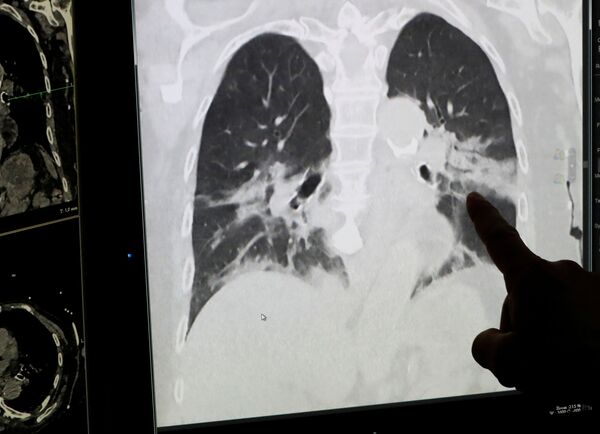

Như ấn phẩm địa phương Focus đưa tin hôm thứ Năm, ca phẫu thuật đã được thực hiện thành công mười ngày trước và hiện tại tình trạng của bệnh nhân được đánh giá là tốt. Được biết, thanh niên người Ý 18 tuổi có vóc dáng thể thao và không mắc bệnh mãn tính, nhưng sau khi bị nhiễm COVID-19, anh đã phải chữa trị hai tháng trong phòng chăm sóc đặc biệt của bệnh viện San Raffaele. Toàn bộ thời gian này anh phải thở máy, vì coronavirus gần như phá hủy hoàn toàn phổi của anh. Các bác sĩ kết luận rằng trong tình huống này, chỉ làm phẫu thuật ghép phổi mới có thể cứu được bệnh nhân trẻ tuổi.

"Cấy ghép phổi bao giờ cũng là ca phẫu thuật khó khăn, và khi bệnh nhân mắc COVID-19 và đang trong tình trạng nguy kịch thì đó thực sự là thử thách lớn đối với chúng tôi", - ông Mario Nozotti, giám đốc Dịch vụ Phẫu thuật lồng ngực nói với các phóng viên.